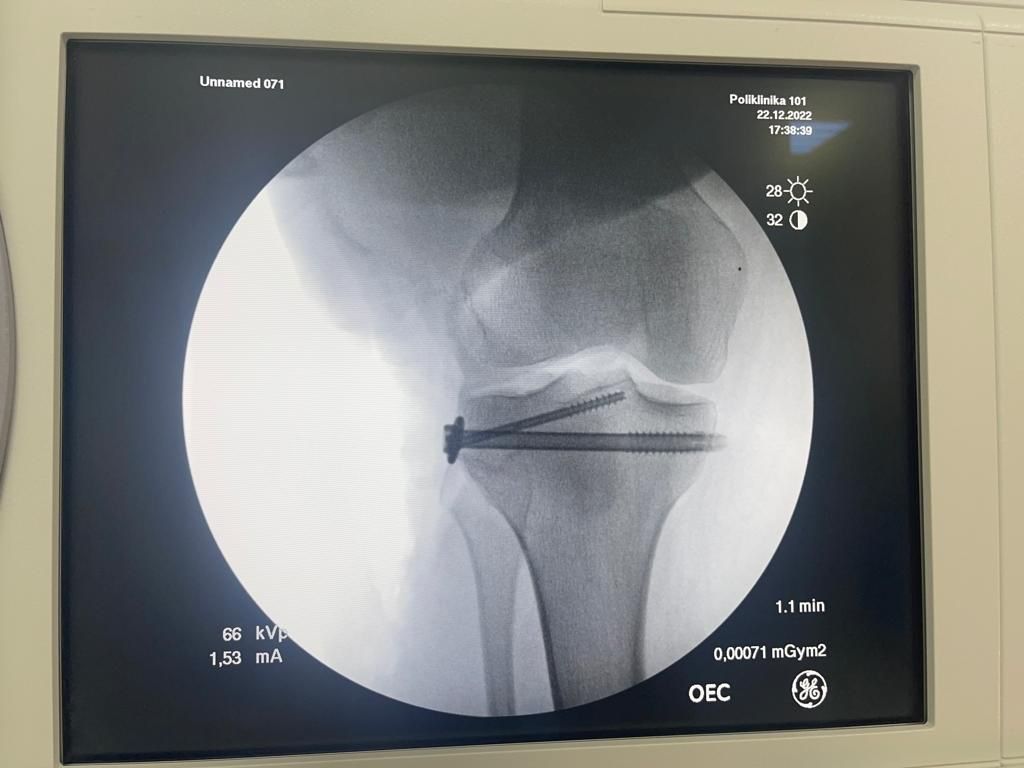

В 2022 году обратились к Николай Николаевичу уже с мужем, тоже травма коленного сустава только уже порвал задний крест, все так же МРТ , консультация и вот мы уже готовимся к операции! Прошло все быстро, муж четко соблюдал все рекомендации следовал всем предписаниям , реабилитация и вот он так же быстро восстановился и вернулся к активному образу жизни, занимается спортом- велосипед, бег, зал- колено как новое, не беспокоит, а главное стабильное! Мы довольны! Спасибо огромное за лечение, за его волшебные руки, я рекомендую этого специалиста, как человека и профессионала- проверено годами))))

Фото после пластики ЗКС

Фото к отзыву о Гнелица Николай Николаевич